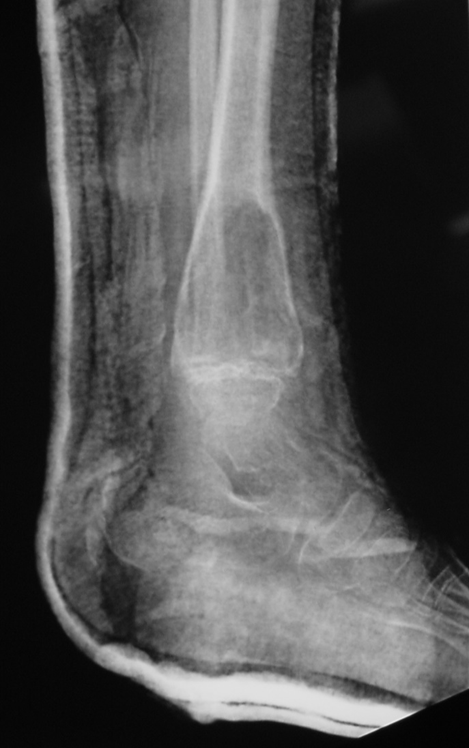

Radiographic Presentation

• Variable sizes

• Multiple internal trabeculations

• Rapid growth

• Cortical scalloping, bone contour often expanded.

Plain x-ray

• Radiolucent

• Geographic and Eccentric lesion that is well circumscribed

• May scallop or expand the surrounding cortex

• Surrounded by sclerotic bone

• Methaphyseal region most common

• Eccentric

• Elevation of the periosteum could be seen as a benign appearing periosteal reaction (continuous periosteal reaction)